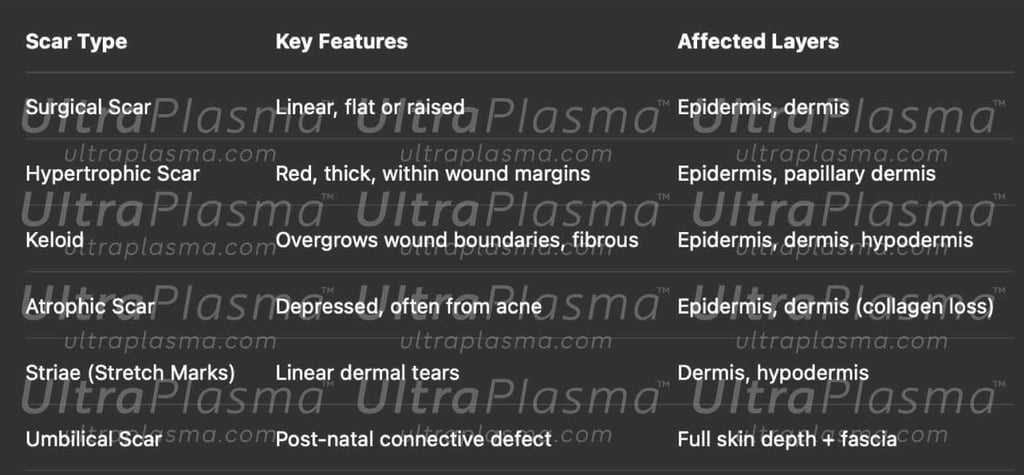

2.Scar Typology and Pathophysiology

Scars can result from trauma, surgery, acne, burns, or infections. Classified as:

Atrophic scars (e.g., acne pits)

Hypertrophic scars (confined, raised fibrous tissue)

Keloids (invasive fibrotic overgrowths)

Contracture scars (post-burn tightening)